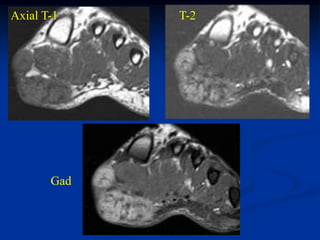

Case #251

11 year male with desmoid foot

Sagittal T-1 MRI

Axial T-1 MRI

Axial T-2 MRI